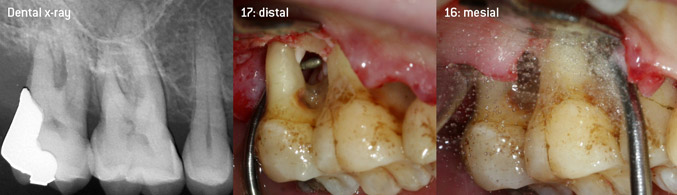

Come pionieri dello sviluppo della nuova punta per ablatori 3AP diamantata, i due dentisti hanno riconosciuto la necessità di migliorare le restrizioni di manipolazione delle punte diamantate disponibili in commercio, specialmente durante il trattamento della forcazione e lavorando su tasche intraossee strette. Tutto ciò deve essere fattibile sia per procedure non chirurgiche (figura 2) sia per procedure chirurgiche (figura 3).

(Foto (figure 2-4): © Dott. Christian Graetz)